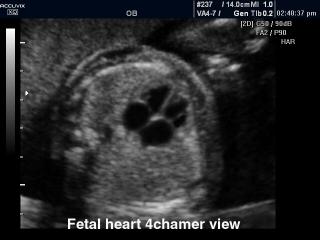

Atlas of ultrasound images - obsterics (pg. 10)

In the section "Оbsterics" of atlas the results of ultrasonic examinations of pregnant women with different durations of gestation are represented. Here you can see images of internally organs, cerebrum, cordis and the sex of the fetus, the sonograms of multiple pregnancy, the blood flow in placenta and umbilical cord, defects of fetal`s development, etc.